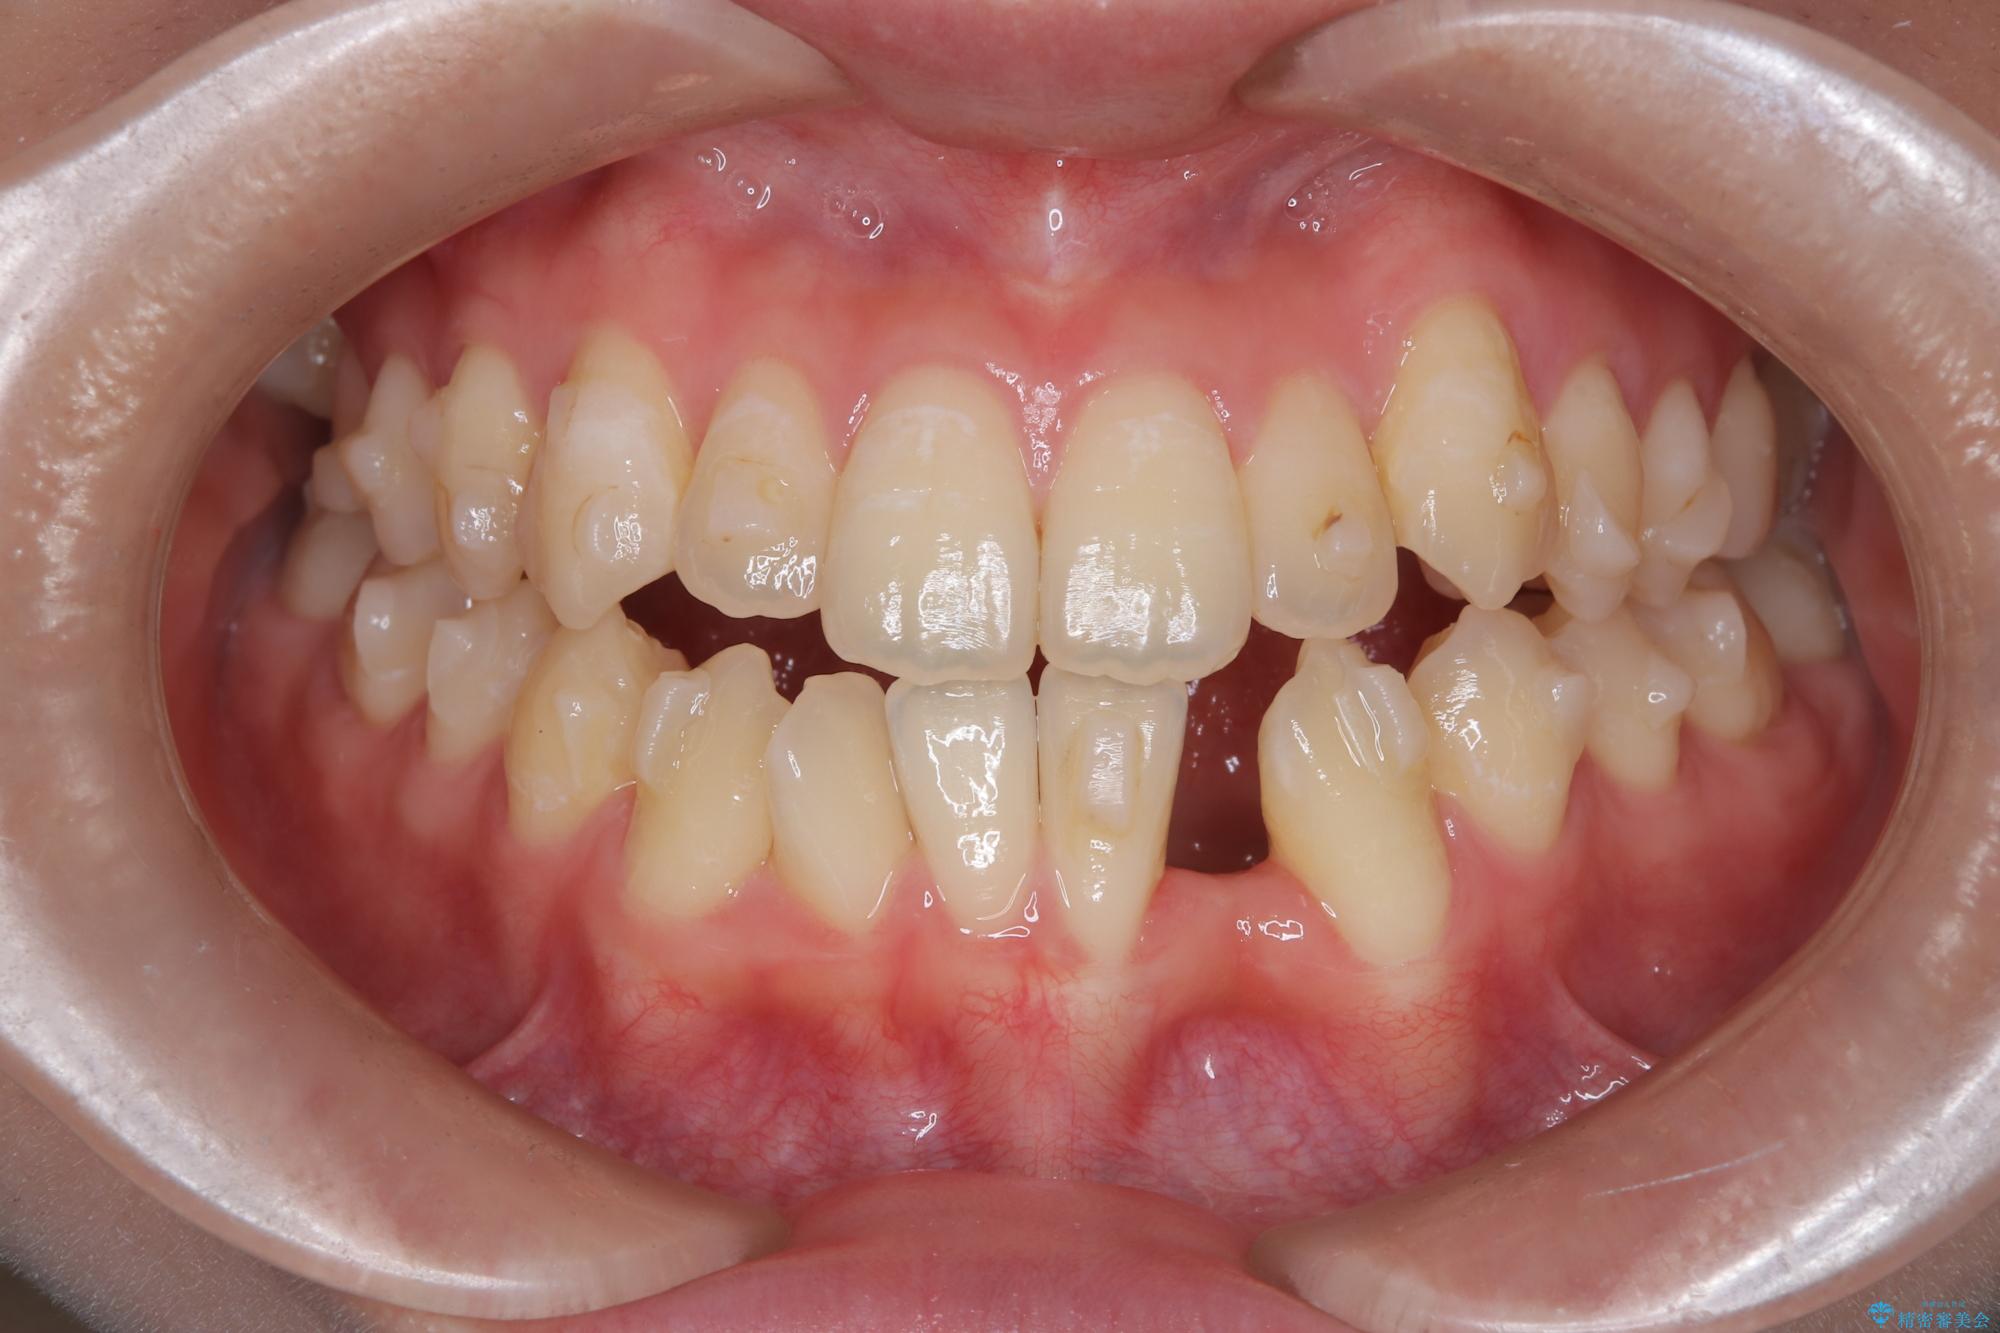

- 他院でインビザライン矯正を行っていたものの、通院先の閉院により治療が継続できなくなったとのことで来院されました。

診査の結果、すでに下顎前歯の抜歯が行われていましたが、マウスピースの適合が著しく悪くなっており、歯が計画通りに動いていない状態でした。また、歯を支える骨の厚みや歯肉の薄さを考慮すると、このままマウスピースによる傾斜移動を続けるのは歯肉退縮(歯茎が下がること)のリスクが非常に高いと判断。